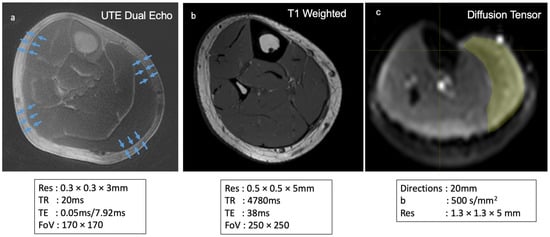

The work presented here involved three imaging protocols: a dual-echo UTE, a T1-weighted scan, and DTI (Figure 10). Tractography data from DTI may be used to provide context to connective tissue imaging—the endpoints derived from DTI tracts indicate regions corresponding to deep fascia versus regions corresponding to aponeuroses, where aponeurosis tissue coincides with regions of tract endpoints from DTI. Additionally, DTI data may be used to compute parameters of muscle architecture, such as fascicle length, pennation angle, and physiological cross-sectional areas.

Figure 10.

Summary of sequences used for imaging deep fascia, muscle fibers, and other connective tissue structures. Axial (a) dual-echo UTE subtraction imaging primarily highlights the deep fascia, providing detailed insights into its structure. Axial (b) T1-weighted imaging is used to visualize the anatomical structure of lower leg muscles, enabling accurate muscle volume calculations. Axial (c) DTI is employed to assess muscle fiber architecture, including measurements of fascicle length, pennation angle, and physiological cross-sectional area (PCSA).

The following parameters were used for T1-weighted imaging: TE = 38 ms, TR = 4780 ms, slice thickness 5 mm, matrix size = 1024 × 1024, FOV = 250 × 250 mm, in-plane resolution = 0.5 mm × 0.5 mm. For DTI, a spin echo echoplanar imaging (EPI) sequence was used with slice thickness = 5 mm, in-plane resolution 1.3 × 1.3 mm, 64 slices, TR/TE = 2887/49 ms, number of signal averages = 1, diffusion directions = 20, b = 500 s/mm2, and a reference image with b = 0 s/mm2.